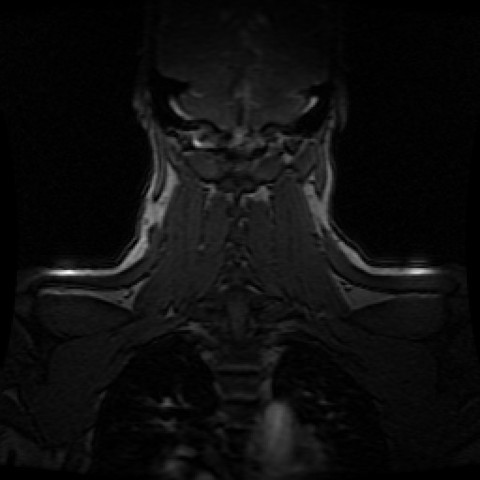

Hallo natürlich weiß ich das hier keine Diagnosen gestellt werden könnenAber vielleicht kennt sich ja jemand hier ein wenig mit der Deutung von MRTAufnahmen aus und hat eine Idee?Auf meinen Bild ist 1 weiß leuchtende Punkt zusehen zu sehen auf der Rechte Seite. Selten wird eine CT oder MRT zur Identifikation erforderlich Die häufigste, benigne echoreiche Läsion der Leber ist mit bis zu Prozent das Hämangiom, wobei Frauen sechsmal häufiger betroffen sind Die Größe kann zwischen wenigen Millimetern und über cm liegen, und ab 4 cm Größe werden diese Raumforderungen im. Es kommt zu einer Minderdurchblutung des Rückenmarks (‚weißer Fleck,‘ auch als Myelomalazie bekannt), die für die Symptome einer Myelopathie verantwortlich ist In den Schichtaufnahmen der Magnetresonanztomografie (MRT) ist die Myelomalazie (heller Fleck) klar erkennbar.